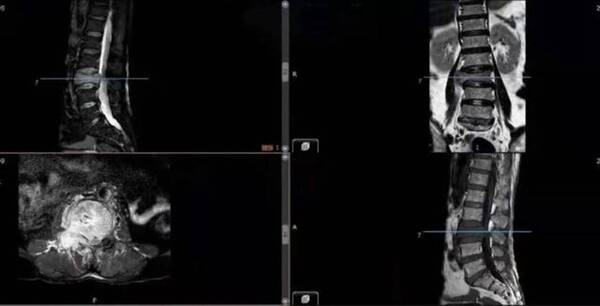

MRI顯示:L3椎體被腫瘤完全破壞,右側(cè)神經(jīng)受壓明顯。

3D打印術(shù)后人工椎體植入脊柱重建良好。